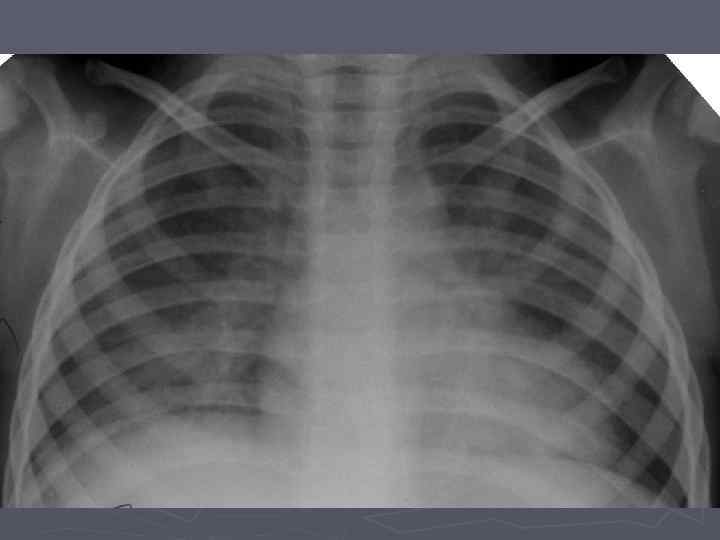

Клинико-эпидемиологические особенности туберкулезной инфекции у ВИЧинфицированных и больных СПИДом детей ► Вертикальный путь заражения ВИЧ; ► Ранний возраст; ► Семейные контакты с болеющими туберкулезом в активных фазах; ► Отсутствие вакцинации БЦЖ; ► Выраженный локальный процесс, протекающий с: § бронхолегочными поражениями; § Распадом легочной ткани; § Обсеменением легочной ткани.

Неблагоприятное сочетание ряда обстоятельств: § Ранний возраст; § Тяжелые семейные контакты; § Отсутствие вакцинации - и у свободных от ВИЧ-инфекции детей всегда приводят к развитию локального туберкулеза, протекающего, как правило, ОСЛОЖНЕННО с бронхолегочными поражениями, распадом легочной ткани, диссеминациями.